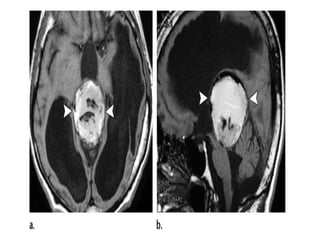

a)Sagittal T1 weighted MR

image shows an

heterogeneous pineal region

mass with foci of T1

shortening due to

hemorrhage , note the

associated hydrocephalus

b)Axial postcontrast T1-

weighted MR image shows

that the pineal region mass

also has an heterogeneous

enhancement with foci of

necrosis/cyst , involvement of

the tectal plate and both

thalami are also present (not

shown) , evaluation of serum

oncoproteins demonstrated

high level of b-hCG , biopsy of

the lesion revealed that it

corresponds to

Choriocarcinoma